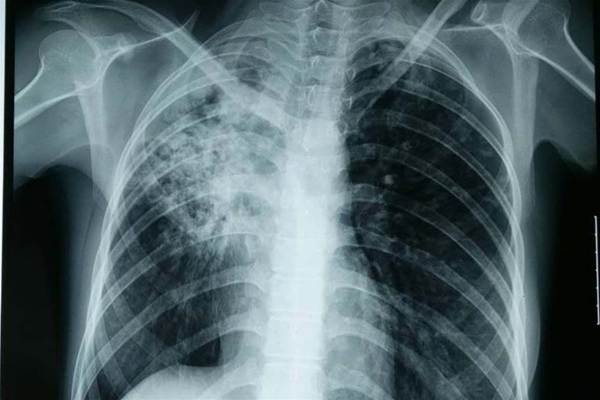

大马肺结核(TB)疫情拉响警报!卫生部长拿督斯里祖基菲里透露,截至今年2月7日,全国已有7个州属相继爆发共10个新的结核病感染群。其中,柔佛州的情况最令人担忧,不仅出现单一群组高达37宗病例的记录,更因一名确诊的72岁老妇,导致多达903人被列为密切接触者!

为了围堵疫情,卫生部已锁定寄宿学校及监狱等高风险机构,严格执行2018年结核病信息系统手册的筛查流程。部长提醒,若民众出现长期咳嗽、反复发热、食欲减退或体重不明下降等症状,务必提高警惕。

值得关注的是,并非所有结核病都具备传染性。山姆加纳丹医生科普道,传播风险主要源自活动性肺结核,病菌通过空气飞沫传播;而肺外结核(如影响骨骼、淋巴或脊柱)通常不涉及呼吸道,因此不具传染性。他呼吁公众科学理性看待结核病,避免对患者产生不必要的恐慌或污名化,但必须确保确诊者完成整个疗程,严禁中途停药,以免产生更具威胁的“耐药性”结核病。